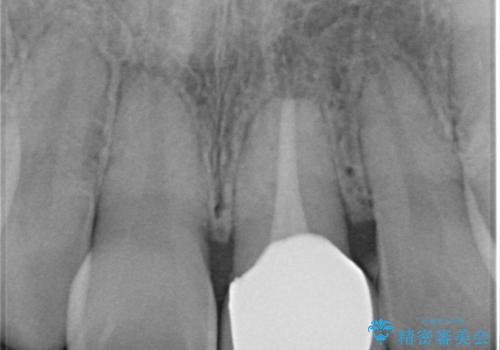

- 神経の治療をしたまま放置していた歯が、変色してきたので改善したい。と前歯の審美性の改善を求めて来院されました。

根管治療後の歯には部分的な修復処置が為され、変色が進行している状態でした。

ジルコニアクラウンを用いて、自然な色調となるよう治療を計画します。

根管治療は行わず、仮歯・ジルコニアクラウンのみの処置を行い自然な歯に仕上げることができました。